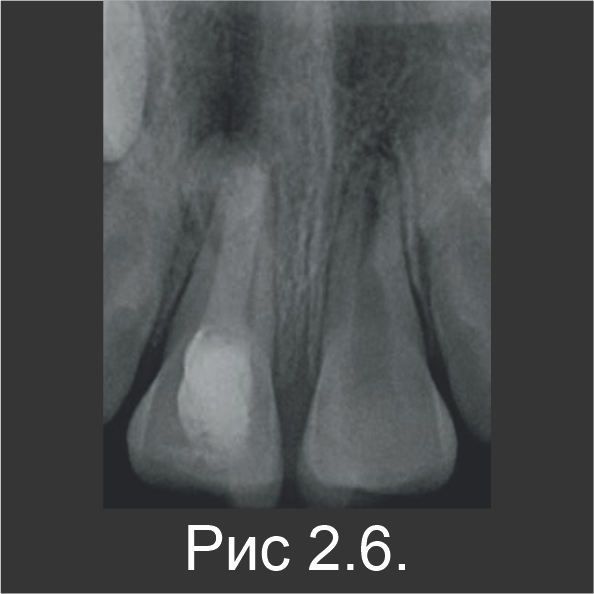

Сообщений о боли и чувствительности после лечения не было.Спустя 2 месяца, свищ исчез, а ткани зажили (рис. 2.5). На рентгенограмме заметна постепенная резорбция вышедшего материала (рис. 2.6).